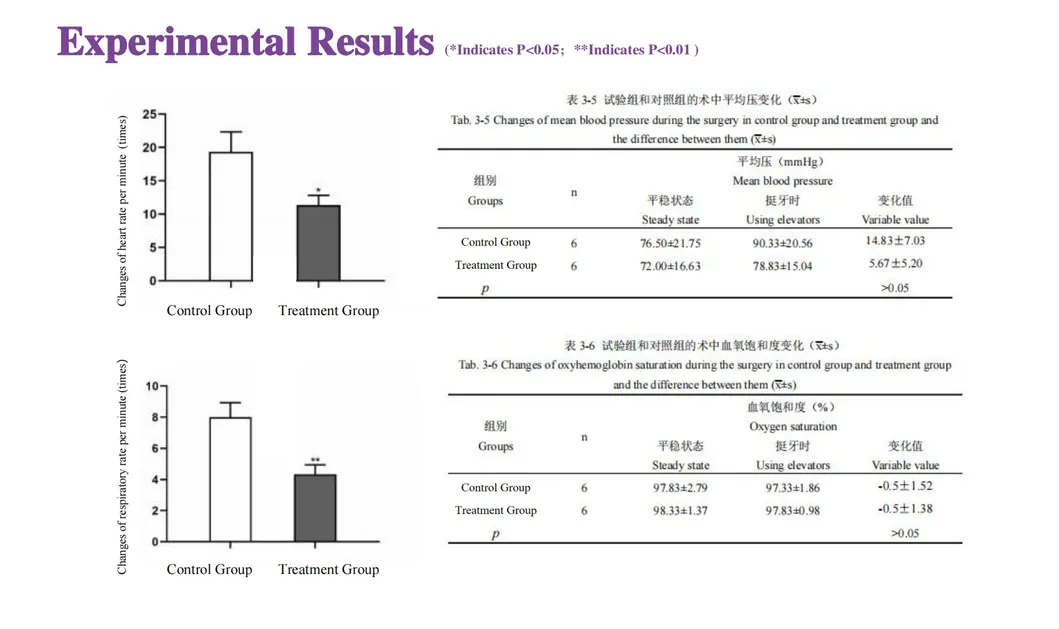

In this groundbreaking study, dogs were selected to assess the effectiveness of the Golden Cudgel-Pneumatic Dental Elevator Kit. Researchers meticulously documented physiological parameters, extraction duration, and socket damage compared to traditional manual devices. The data provides profound insights into the superior performance and efficiency of these advanced dental tools.